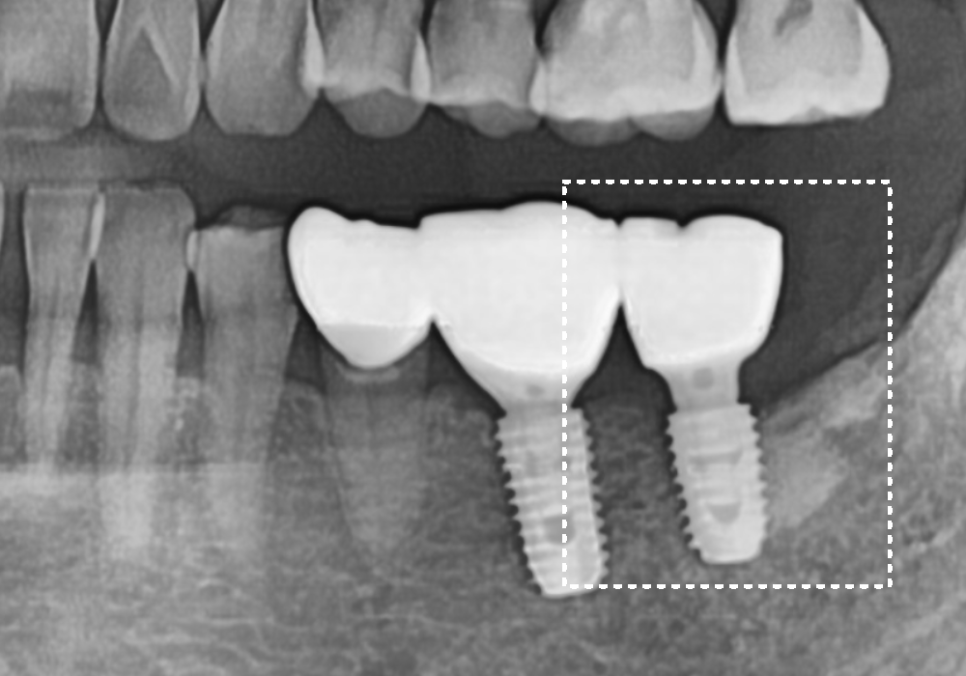

| 1) 오른쪽 어금니#47,48 어금니들이 빈 곳으로 많이 쏠려 #46 상실 부위에 임플란트를 심을 공간이 부족한 상태2) 왼쪽 어금니위쪽 어금니(#27)가 맞물릴 곳이 없어 아래로 정출되어 내려온 상태 |

오른쪽 어금니 치료 과정

발치 후 빈 공간, 이 빼고 오래 냅두면 이렇게 됩니다.

230420

치아들이 빈 공간 쪽으로

심하게 쓰러져버린 탓에,

정작 임플란트를 심을 자리가

도저히 나오지 않는 상황..!

결국, 고민 끝에 교합을 크게 바꾸지 않으면서

빈 곳을 채우는 브릿지로 치료를 결정했습니다.

현재 치아가 많이 기울어져 있기 때문에

치아를 깎는 양이 많을 것으로 예상되었는데요~

시린 증상을 방지하기 위해

꼼꼼하게 신경치료를 선행한 뒤

브릿지로 마무리해드렸습니다~

230704